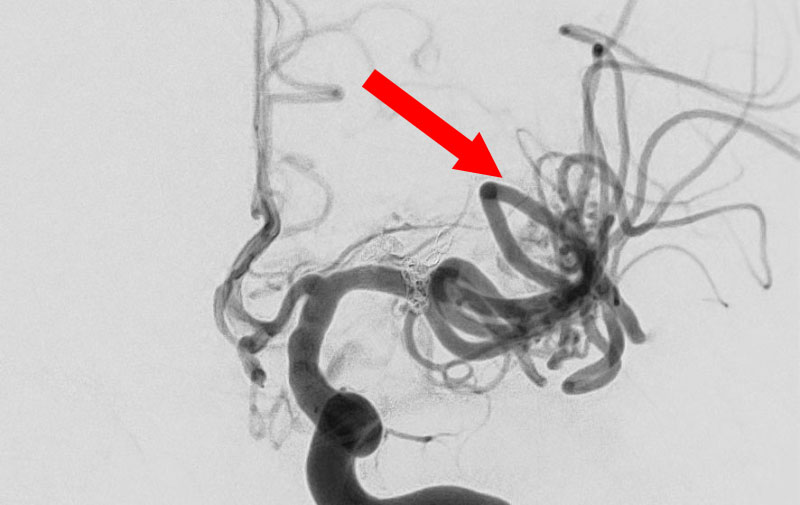

No.1576 手術前

No.1576 手術中

No.1576 手術後